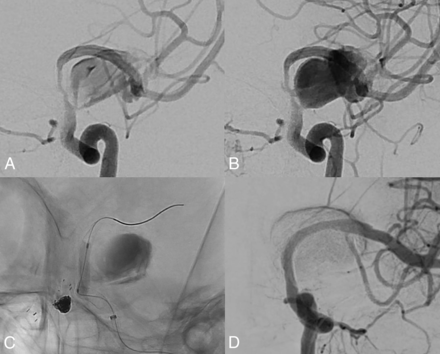

In this study, it was confirmed that the presence of incorporated vessels (OR = 0.13, P = .021) was a significant factor in predicting the effects of FD. Among cases with no incorporated vessel, 22/29 (75.8%) showed the effect of FD, whereas in cases with incorporation, only 12/22 (54.6%) cases showed the effect of FD. In patients exhibiting remnant entry or subtotal filling on follow-up angiography, a significant proportion of aneurysms developed thromboses and occlusion, but sometimes remnant aneurysms were apparent close to the incorporated vessels (Fig 2). Bender et al12 studied a single-institution series of 445 cases and reported that vessel incorporation was a risk factor for incomplete occlusion after FD (OR = 2.206, P = .035).

Remnant aneurysms are apparent close to the incorporated ophthalmic artery on 6-month follow-up angiography.